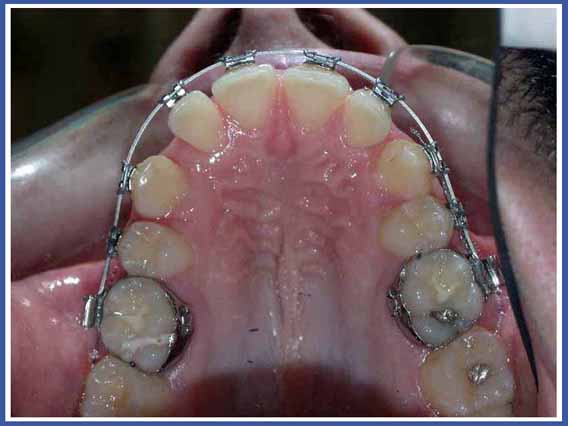

סמכים אורתודונטים (גשר) Brackets:

האמצעי הנפוץ ביותר כיום להזזת שיניים. הסמכים המודבקים לשיניים והחוט שעובר ביניהם מאפשרים להזיז את השיניים בכל שלושת המימדים בשליטה מלאה על התנועה, בניגוד לפלטות שיכולות להזיז שיניים רק בהטיה (רק לשנות את הזווית של השן בלסת). סמכים יכולים להיות מתכתיים או שקופים.

לסמכים המודבקים לשיניים יש יתרונות רבים אך יש להם גם חסרונות. החסרון העיקרי הוא הצטברות שאריות מזון וחיידקים עליהם. כדי למנוע סכנה לעששת (חורים) מסביב לסמכים, יש להקפיד על צחצוח שיניים קפדני במהלך הטיפול, ולהמנע ככל האפשר ממזון המזרז את התפתחות העששת (מזון עשיר בסוכר).

הנחיות לשמירה על הגיינה בזמן הטיפול האורתודונטי באמצעות סמכים (גשר):

חשוב מאד לנקות בין השיניים והטבעות, שכן לחיידקים יש נטייה גדולה יותר להימצא במקומות אליהם קשה לנו להגיע. פעולה זו תמנע בעיות ועששת גם לאחר סיום הטיפול והורדת הסמכים.